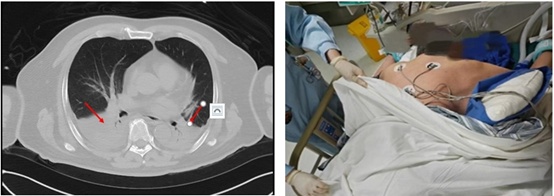

转入ICU时冯大爷处于极度呼吸窘迫状态,心率130次/分,呼吸频率40次/分,腹部胀痛异常明显,腹内压明显升高,腹部触之如石头般坚硬,四肢湿冷,生命危在旦夕!ICU医生立即给予气管插管接呼吸机辅助呼吸,患者重度呼吸窘迫综合征。同时继续给予稳定血压、禁食、抑制胰液分泌、抗炎、通便等治疗,给予纤支镜检查并清理气道分泌物。考虑患者急性重症胰腺炎,伴炎症因子风暴,导致多脏器功能受损,给血液净化治疗,优化液体管理的同时清除炎症因子。经过积极治疗冯大爷病情终于得到了有效的控制。在治疗的第3天,患者开始排便,腹部开始变软,吸氧浓度也从100%降到70%,于是给予患者安置鼻空肠管,逐渐开放肠内营养。随后的一周,各项指标均好转,呼吸情况却未再进一步好转,无法拔除气管插管,复查胸部CT提示双下肺坠积性肺炎,于是给予患者进行了俯卧位通气,并加强呼吸道管理。在我科治疗的第3周,患者顺利拔除了气管插管。拔管后第3天顺利转消化内科普通病房继续治疗,并在2周后顺利康复出院。